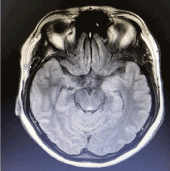

Case history

Figure3.Magnetic resonance imaging demonstrating bilateral hippocampal high intensity signal on T2/Flair weighted images